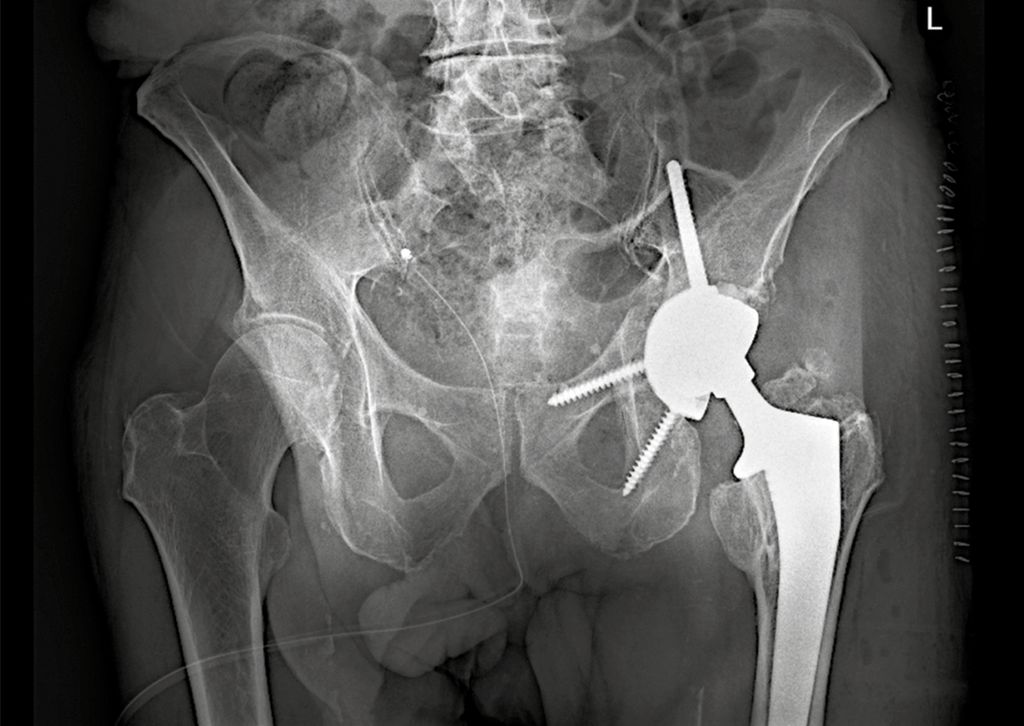

Implantation der PRS-Rekonstruktionspfanne

Die PRS-Pfanne zeichnet sich durch ihre massive Bauweise, multiple Schraubenoptionen und die Möglichkeit einer zentralen Ileumschraube aus. Nach Einbringen der Pfanne wird diese korrekt ausgerichtet (Inklination ca. 40–45°, Anteversion ca. 15–20°). Der entscheidende Schritt ist die Platzierung der zentralen Ileumschraube. Dafür wird unter Bildwandlerkontrolle ein Bohrdraht in den supraazetabulären Korridor gesetzt (Abb. 3a u. 3b) und mit dem 6-mm-Bohrer überbohrt. Anschließend wird die Schraube durch das entsprechende Positionsloch der Pfanne in den supraazetabulären Anteil des Iliums eingebracht. Dabei ist auf eine ausreichende Schraubenlänge zu achten, um eine stabile Verankerung zu erzielen. Die zentrale Schraube übernimmt eine lasttragende Funktion und wirkt wie eine intrapelvine Abstützung. Zusätzlich wird die Pfanne mit Schrauben im Sitzbein und/oder dem Schambeinast fixiert (Abb. 4). Die PRS-Pfanne erlaubt hierbei eine flexible Schraubenplatzierung, was insbesondere bei komplexen Frakturmorphologien von Vorteil ist.

Dank der hohen Primärstabilität der Konstruktion wird eine frühfunktionelle Behandlung angestrebt. Die Patient:innen können unter physiotherapeutischer Aufsicht vollbelastend mobilisiert werden. Dies stellt einen wesentlichen Vorteil gegenüber der alleinigen Osteosynthese dar, insbesondere bei geriatrischen Patientinnen und Patienten. Eine radiologische Verlaufskontrolle wird postoperativ sowie nach sechs und zwölf Wochen empfohlen.